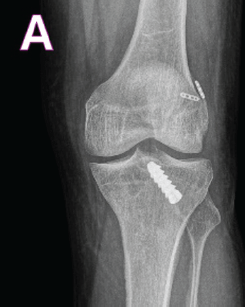

Single Stage Revision Anterior Cruciate Ligament Reconstruction through Anterolateral Tunnel in a Significantly Widened Tibial Tunnel using Peroneus Longus Tendon Autograft – A Case Report

Sujit Jos , Athish James , Prannoy Paul , Rakshit Jayaram , Antony Joseph

………………………………p.84-88